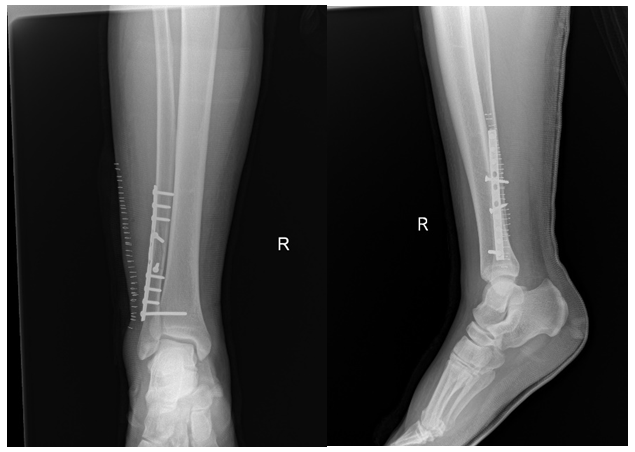

Primary right Ankle X-rays done at trauma bay (Figure 1). AP and lateral X-rays of right ankle showing after fixation (Figure 2). After 8 weeks patient underwent synedsmotic screw removal (Figure 3), and he noticed big toe deformity. At 1 year follow up patient booked for implant removal and was still complaining of same deformity and underwent FHL lengthening at same time.

Figure 2 AP and lateral X-rays of right ankle showing after fixation.

Patient was operated as a lateral malleolus fracture by plate along with syndesmotic screw.